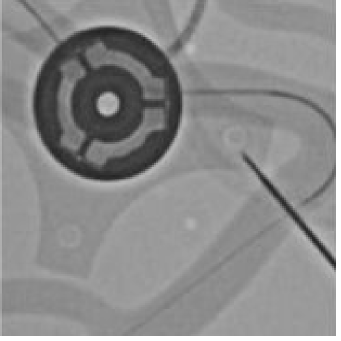

Robotic Setup. To collect large-scale X-ray images, we employ a robotic platform and a full-size silicon phantom. A surgeon uses a master device joystick to control a follower robot for cannulating three arteries: the left subclavian (LSA), left common carotid (LCCA), and right common carotid (RCCA). Fig. 3 shows an overview of our robotics setup. During each catheterization procedure, the surgeon activates the X-ray fluoroscopy using a pedal in the operating room. The experiments are conducted using the Epsilon X-ray Generator. We develop a real-time image grabber to transmit the video feed of the surgical scene to a workstation, a computer-based device equipped with an 8-Core ARM v8.2 64-bit CPU. Overall, we collect and label 4,700 new X-ray images to create our EIPhantom dataset.

(a) Controller

(b) Robotic Platform